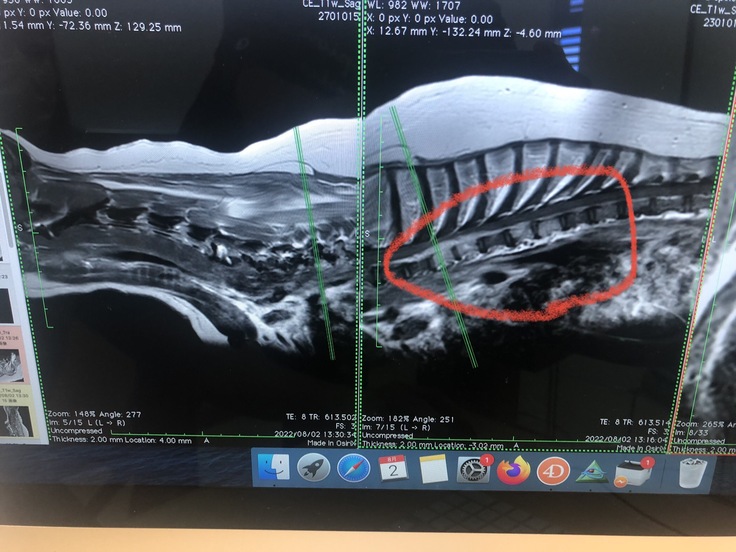

※腫瘍部を拡大して画像になります、縦に白い柱が、腫瘍に侵されてしまった骨です

左側、白い骨の上部に細長い雲の様に見える物も腫瘍です。

赤丸の中、縦に白くなっている部位が、腫瘍に侵された骨です、

左側2本の白い部位の上に細長い白い雲のような物も腫瘍になります。

赤丸、左側が、1年4ヶ月前に発症した、最初の病巣になります、

約3センチ下に、今回の病巣になります。この腫瘍が、後ろ足の麻痺、排尿困難を引き起こして

います。同時に痛みも。